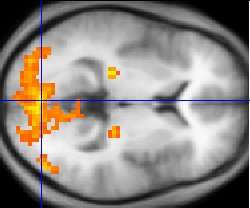

Functional MRI

Functional MRI (fMRI) is used to understand how different parts of the brain respond to external stimuli or passive activity in a resting state. Blood oxygenation level dependent (BOLD) fMRI measures the hemodynamic response to transient neural activity resulting from a change in the ratio of oxyhemoglobin and deoxyhemoglobin. Researchers use statistical methods to construct a 3D parametric map of the brain which indicates the regions of the cortex that demonstrate a significant change in activity in response to the task. fMRI has applications in behavioral and cognitive research, and in planning neurosurgery of eloquent brain areas.[29][30]

Functional MRI (fMRI) measures signal changes in the brain that are due to changing neural activity. Compared to anatomical T1W imaging, the brain is scanned at lower spatial resolution but at a higher temporal resolution (typically once every 2–3 seconds). Increases in neural activity cause changes in the MR signal via T*

2 changes;[168] this mechanism is referred to as the BOLD (blood-oxygen-level dependent) effect. Increased neural activity causes an increased demand for oxygen, and the vascular system actually overcompensates for this, increasing the amount of oxygenated hemoglobin relative to deoxygenated hemoglobin. Because deoxygenated hemoglobin attenuates the MR signal, the vascular response leads to a signal increase that is related to the neural activity. The precise nature of the relationship between neural activity and the BOLD signal is a subject of current research. The BOLD effect also allows for the generation of high resolution 3D maps of the venous vasculature within neural tissue.

While BOLD signal analysis is the most common method employed for neuroscience studies in human subjects, the flexible nature of MR imaging provides means to sensitize the signal to other aspects of the blood supply. Alternative techniques employ arterial spin labeling (ASL) or weighting the MRI signal by cerebral blood flow (CBF) and cerebral blood volume (CBV). The CBV method requires injection of a class of MRI contrast agents that are now in human clinical trials. Because this method has been shown to be far more sensitive than the BOLD technique in preclinical studies, it may potentially expand the role of fMRI in clinical applications. The CBF method provides more quantitative information than the BOLD signal, albeit at a significant loss of detection sensitivity.